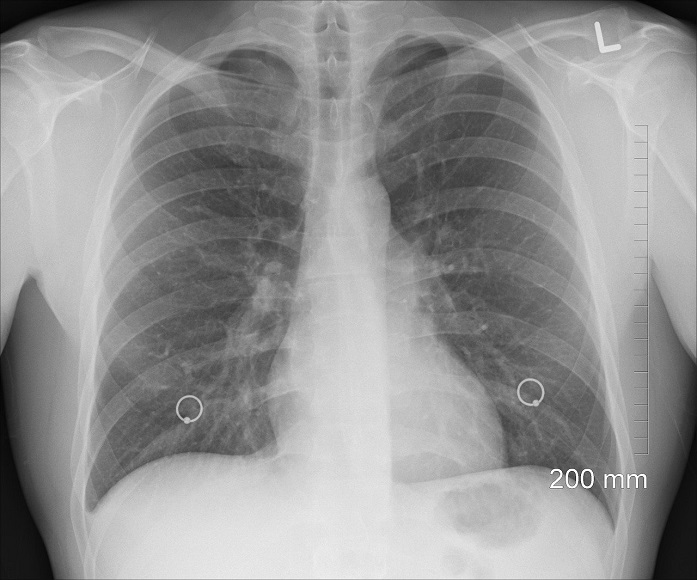

Nach mehr als fünf Wochen galten die Taucher als genesen. Hartig bittet sie für eine kleine Nachuntersuchung ins Spital zu kommen. Dann der schreckliche Befund der Röntgenbilder: „Die Schäden an der Lunge sind irreversibel“, sagt Hartig der APA.

„Die massiven Veränderungen an der Lunge können die Unfallgefahr deutlich erhöhen“ sagt der Oberarzt Frank Hartig.

„In der Bildgebung wurden sie überhaupt nicht besser“, berichtete Hartig.